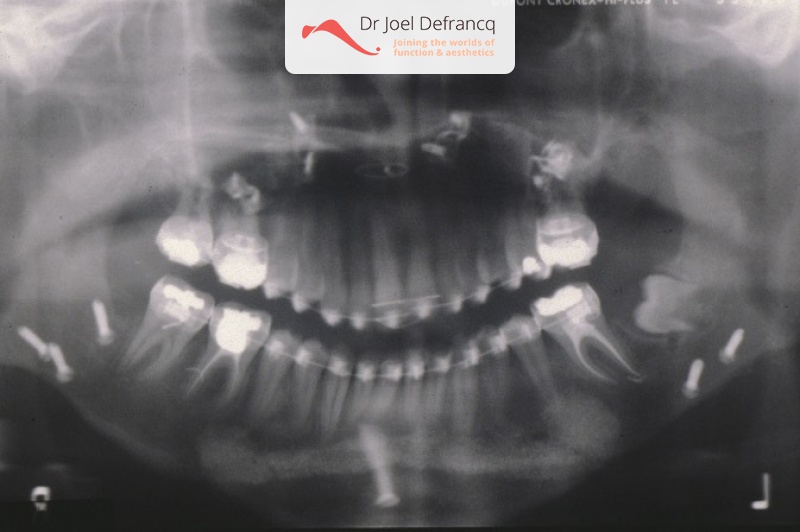

Darsa: Bovenkaak te groot en te veel naar voor

Kaakchirurgie

- Verlenging onderkaak (BSSO)

- Naar achter plaatsen bovenkaak (Le Fort I)

- Kinchirurgie

- Bovenkaak werd tevens versmald via midline split